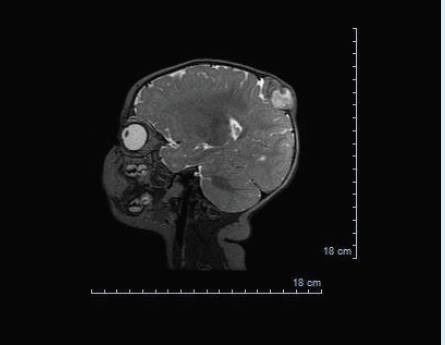

tumor

Mariam Fahim, DO; Judith Oh Leonor, OMS-IV

A male born via normal spontaneous vaginal delivery with unremarkable prenatal labs was noted to have a 1-cm lesion near the vertex of the skull.